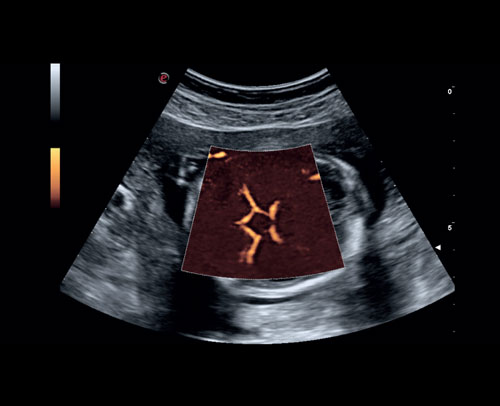

Fetální Willisův kruh s Power Dopplerem.